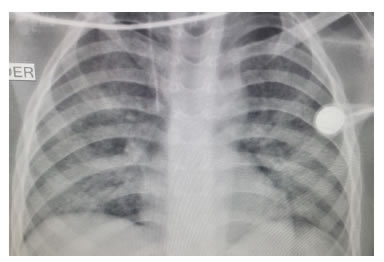

Presentó un cuadro clínico de dolor abdominal, obstrucción intestinal y ascitis de un mes evolución; además, síndrome de respuesta inflamatoria sistémica que produjo taquicardia y fiebre. Se requirió su hospitalización y la práctica de una laparotomía de urgencia. En la ecografía abdominal total se encontró líquido libre en la cavidad abdominal y, la tomografía computadorizada de abdomen contrastada con medio hidrosoluble, un neumoperitoneo masivo (figura 2).

Esto hace que el diagnóstico se haga tardíamente, con un promedio de 2,6 meses entre el inicio de los síntomas y el diagnóstico; en este caso, fue inferior a lo reportado en la literatura científica. Es importante establecer si ha existido contacto con individuos con tuberculosis activa, ya que hasta 66,7% de los pacientes con tuberculosis peritoneal han estado expuestos, como en este caso. Además, la peritonitis tuberculosa debe incluirse en el diagnóstico diferencial en casos de ascitis de origen no claro, como lo recomiendan Sanai, et al., en una revisión sistemática 3. La prueba de tuberculina es positiva en 18 a 27 % de los pacientes, como lo informaron Muneef, et al 11. Los hallazgos físicos y radiológicos de tuberculosis están presentes en 50 a 75 % de los casos, como informaron Cruz, et al., y se asocian con derrame pleural en 12 a 63 %, como en el presente caso 12, 13.

Para el diagnóstico imaginológico, se puede emplear la ecografía abdominal total, la cual permite detectar líquido libre con tabiques finos y linfadenopatías con centro hipoecogénico, que corresponde a necrosis de caseificación. En la tomografía computadorizada de abdomen se aprecia engrosamiento de las asas, especialmente el íleon y la válvula ileocecal, con nódulos en el mesenterio, líquido libre, signos de obstrucción intestinal y perforación 17,18,19.